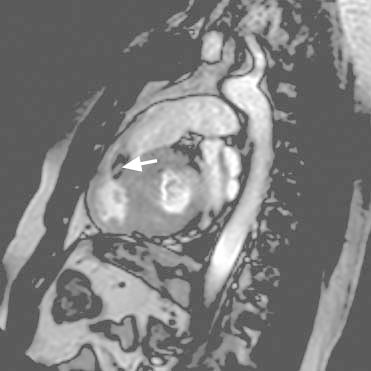

Cardiac magnetic resonance images confirmed noncontiguous hypertrophy involving the basal septal, basal anterior, and apical walls of the left ventricle, as well as the inferior and free walls of the right ventricle (RV). A prominent muscle band in the RVOT contributed to dynamic obstruction across the RVOT (Figs. 4 and 5). Patchy hyperenhancement in the septum, visible in delayed-enhancement sequences after gadolinium administration, was consistent with myocardial fibrosis (Fig. 6). The subendocardium was not involved, suggesting a cause other than coronary disease.

Fig. 4 Cardiac magnetic resonance image shows noncontiguous left ventricular hypertrophy involving the basal septum and apex (arrows).